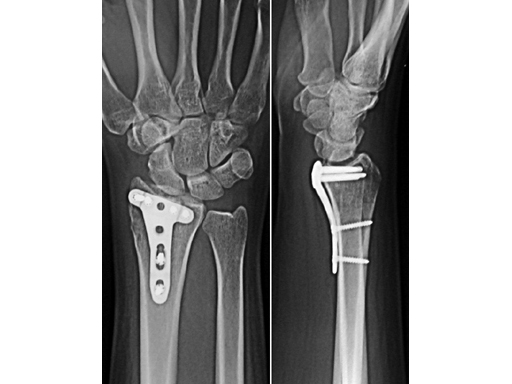

The Locking Distal Radius System 2.4 consists of the new plates: LCP T-Plate 2.4, LCP Radial Column Plate 2.4, LCP L-Plate 2.4, LCP Distal Radius Plate 2.4, dorsal (p-Plate), LCP Volar Plate 2.4, and LCP Volar Buttress Plate 2.4. The 2.4 mm Locking Head Screw, self-tapping, the 2.4 mm Cortex Screw, self-tappingboth with Stardrive recessand special instruments complete the new system. This variety of plates allows fragment-specific treatment of all patterns of distal radial fractures. Indications are simple and displaced extraarticular and intraarticular distal radial fractures and corrective osteotomies of the distal radius. All implants are manufactured in Ti15Mo resulting in excellent bending properties and resistance to fatigue failure, allowing reverse bending. The edges of all plates are chamfered to reduce sharp edges that could contribute to irritation of tendons. Surfaces are polished to minimize tissue adhesion. The distal arms provide a smooth gliding surface for the tendons. Different plate lengths are offered to avoid cutting. The angular stability of the construct allows treatment of osteoporotic bone.